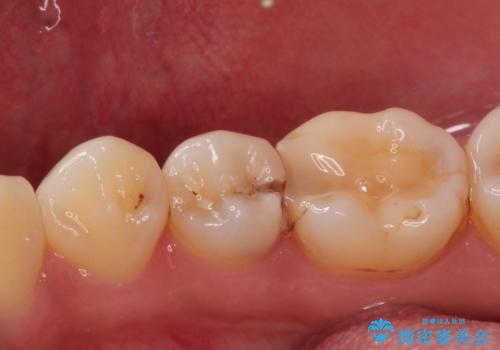

- 歯が欠けて、そこに食べ物が詰まるとのことで来院されました。

虫歯が大きく進行していました。

顕微鏡下で丁寧に虫歯を取り除き、セラミックインレーによる修復治療を行いました。

虫歯が大きく広がっていましたが、顕微鏡を使って慎重に治療を行うことで、神経をとってしまうことなく治療することができます。